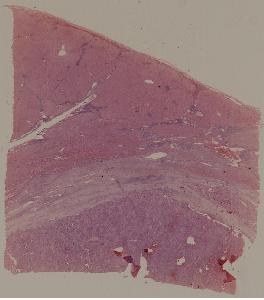

62. Acute viral hepatitis (common type)

63.Chronic active viral hepatitis

64. Acute fulminant viral hepatitis

65. Subacute fulminant viral hepatitis